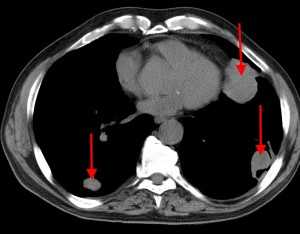

Множественные гематогенные вторичные узлы при раке почки, компьютерная томография (КТ).

КТ: метастазы в легких при раке молочной железы. На изображении справа красной звездочкой отмечен опухолевый узел в молочной железе, красными стрелками - область прорастания опухоли в грудную стенку. Синими звездочками отмечен карциноматозный плеврит — скопление жидкости в плевральной полости. Слева стрелкой отмечен вторичный узел.